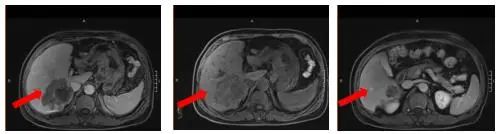

2021-12-21(治疗2周期后) 腹部增强MRI:胃壁增厚较前减轻,腹腔多发肿大淋巴结较前减小、较大者直径约1.6cm,肝脏病灶较前缩小、6.9*5.5cm,评效SD(缩小18%)

图3.治疗2周期后腹部增强MRI影像图

2022-02-04(治疗4周期后)胃壁增厚、腹腔多发肿大淋巴结无明显变化;肝脏病灶继续较前缩小、4.6*3.1cm,部分转移病灶消失,评效SD(缩小27%)

图4.治疗4周期后腹部增强MRI影像图